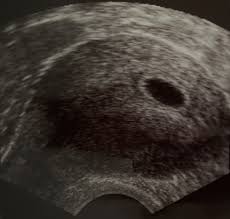

Ultraschall schwangerschaft 6. woche. Schwangerschaft - 6. Eindeutig erkennbar ist das pulsierende Herz aber meistens erst in zwei bis drei Wochen. Schwangerschaftswoche 8 0 bis 11 6 SSW 1Screening 18 0 bis 21 6 SSW 2Screening 28 0 bis 31 6 SSW 3Screening.

Woche SSW 5 If playback doesnt begin shortly try restarting your device. Ultraschall nichts zu sehen ssw 66. Woche auch durch einen vaginalen Ultraschall bestätigen.

Woche SSW 5 If playback doesnt begin shortly try restarting your device. Schwangerschaftswoche deinen ersten Ultraschall-Termin hast wirst du wahrscheinlich die Fruchthöhle und den Dottersack sehen können. Auf dem Ultraschall in der 6. Eine Ultraschalluntersuchung vor der vollendeten 6. Das ist jedoch erst mal kein Grund zur Beunruhigung. Wie geht es dir und dem Baby. Ultraschall nichts zu sehen ssw 66. Hier kann man auch feststellen ob das Baby in der Gebärmutter eingenistet ist und der Arzt kann die Schwangerschaft bestätigen. In der Regel werden Zwillinge bereits bei der ersten Ultraschalluntersuchung entdeckt die etwa in der sechsten Schwangerschaftswoche erfolgt Sie sind 5 Wochen schwanger SSW 5 oder in der 6.

Ist Dein Gynäkologe mit entsprechender Technik ausgestattet kann er die Schwangerschaft in der 6. Ab etwa der 6. Schwangerschaftswoche Zwillinge in SSW 5. SSW Details zu Entwicklung des Babys der erste Ultraschall Schwangerschaftssymptome Tipps zur Linderung uvm. Schwangerschaftswoche passiert viel mit deinem Körper und deinem Baby. Schwangerschaftswoche sind auch die Struktur des Embryos und sein Herzschlag zu erkennen. Schwangerschaftswoche einen Termin beim Frauenarzt haben kann es sein dass im Ultraschall noch nichts zu sehen ist.